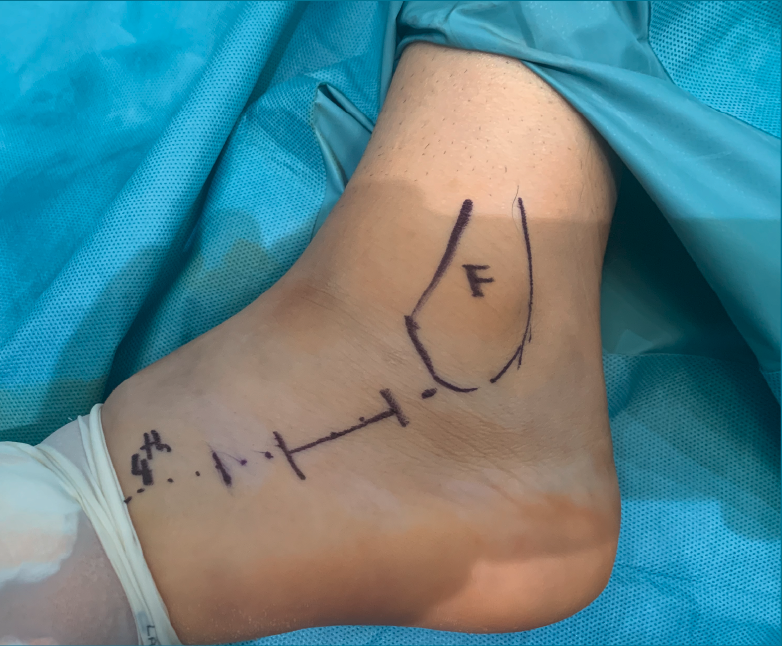

Figura 1. Abordaje del seno del tarso de 2-3 cm. Se realiza una línea que va desde el cuarto metatarsiano (4th) al peroné. F: fíbula.

Para realizar el abordaje del seno del tarso(13) se sigue una línea imaginaria que discurre desde el eje del cuarto metatarsiano hasta la punta del maléolo lateral, realizando una la incisión de 2-3 cm sobre esta línea (se puede ampliar la incisión tanto hacia proximal como a distal) (Figura 1). La disección se debe realizar con cuidado para no dañar el nervio sural ni a los tendones peroneos que cruzan la incisión (Figura 2). Finalmente, se debe abrir el ligamento peroneo-calcáneo para acceder a la articulación subastragalina posterior; este paso no ha demostrado provocar inestabilidad de tobillo durante la evolución posterior.